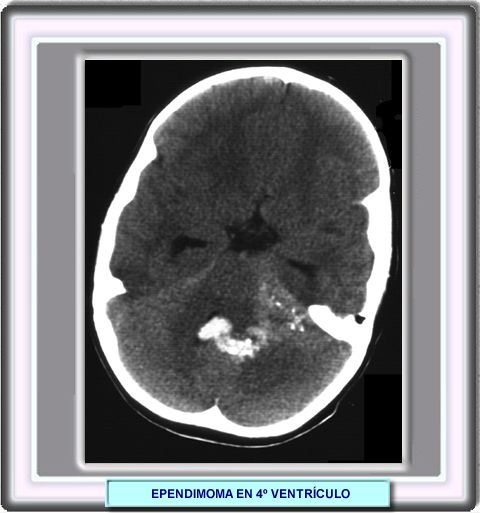

Los ependimomas intracraneales son típicamente isodensos en la TC con un mínimo resaltado cuando se administra un contraste.

Aproximadamente en el 50% de los casos pueden observarse calcificaciones. La formación es quistes es relativamente frecuente en estos tumores así como una extensión de los mismos a la fosa posterior a ravés de los forámenes de Luschka y Magendie.